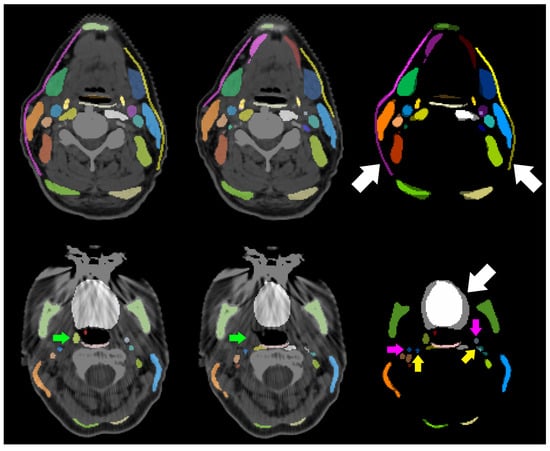

The visual analysis of cases in which the internal carotid artery (ICA) shows especially low DICE and sDICE on both sides, results in four common reasons for deviations between the manual segmentation and its prediction: (a) the ICA is a thin structure, (b) the transition between internal carotid artery and common carotid artery varies, (c) the final slice, on which the ICA occurs cranially varies, and (d) due to metal in the mouth, CT artifacts occur in this area. Figure 5 shows the deviation between manual and predicted segmentation of the ICA due to inconsistent decision on the most cranial slice and the bottom row of Figure 6 shows metal artifacts.

4.2. Inter-Observer Variability, and Tracheostomy Analysis

The anatomical structures with an inter-observer variability outside the 3 σ interval around the mean in any of the three metrics or a value below the Q1 in DICEm or sDICEm or above the Q3 in HDm were visually analyzed. Two systematic reasons are found that explain deviations. First, the lateral extension of the subclavian artery was inconsistent. Second, muscular structures were systematically segmented wider by one observer than by the other. This holds for the prevertebral muscles, the sternocleidomastoid muscles, the trapezius muscles and the digastric muscles. The deviation between all scalene muscles and the tonsils did not follow systematic reasons. Those structures are barely or not visible in the planning CT scans. Figure 6 shows this for the tonsil (green arrows). This results in largely deviating contours between both observers as visualized in the right column of Figure 7. No unambiguous reason can be given for the right internal carotid artery. As it is a thin structure that is difficult to segment, deviations occur in some central slices, while its left counterpart is much better aligned between both observers. No clear difference is visible between both sides of the patient CT scan.